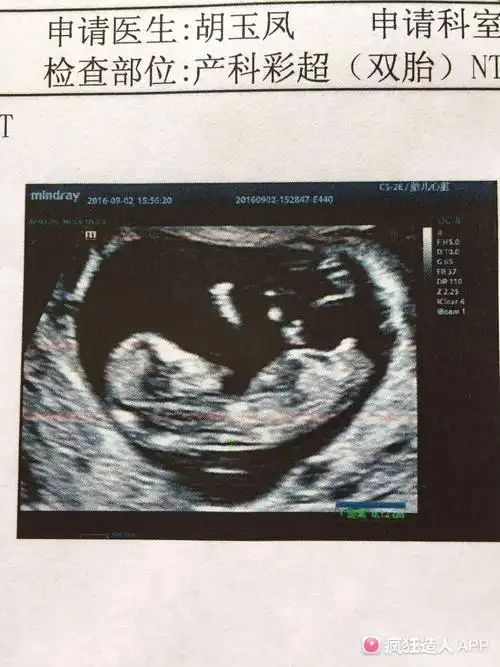

研究nub理论,nt图发来帮看男女,必回

nt怎么看男宝还是女宝 已生宝妈告诉你答案

nt图像上有三个点是怀女孩的概率更高吗?

nt看男女,准确吗?

nt通过啦!有伙伴会看男女嘛